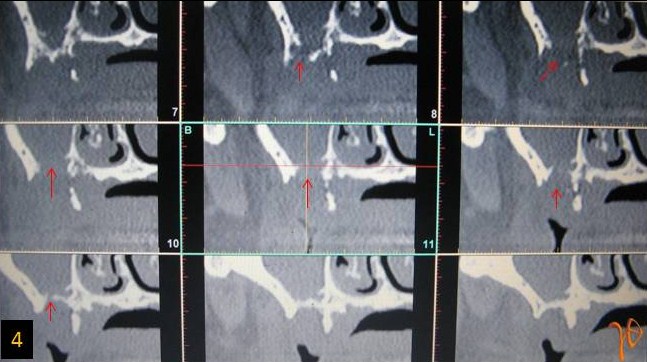

4

Εικ. 4: Στις κάθετες τομές της υπολογιστικής τομογραφίας, κατά μήκος της άνω φατνιακής ακρολοφίας, σημειώνεται(βέλη) η στοματοκολπική επικοινωνία προσθιοπισθίου εύρους 6 mm και μεγίστης διαμέτρου 9 mm.